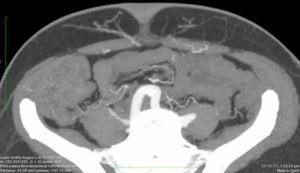

The scan quality achieved was universally excellent (Figure 1). The scan was then reformatted using the OsiriX programme (Figure 2) allowing preoperative planning of which perforators and type of flap to select. Intraoperative findings in both groups were consistent with the preoperative CTAs such that the intraoperative plan did not need to be changed compared with the preoperative findings. There were no complete or partial flap failures.